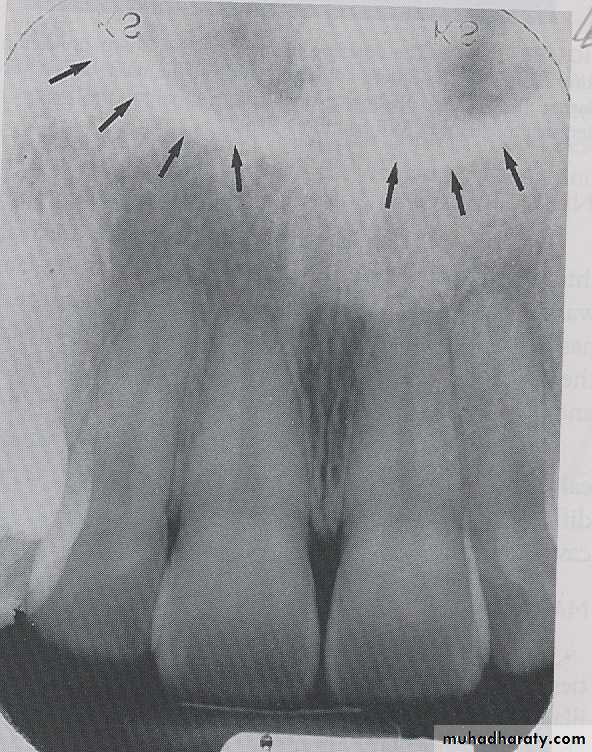

LAMINA DURA: Laminadura is the wall of the tooth socket that surrounds the roots of tooth, on periapical radiograph the laminadura appears as dense radiopaque line that surround the root of a tooth.

ALVEOLAR CREST: The alveolar crest is the most coronal portion of alveolar bone found between teeth. On dental radiograph the alveolar crest appears radiopaque and is typically located 1.5-2mm below the cementoenamel junction

PERIODENTAL LIGAMENT SPACE: The Periodontal ligament space is the space between the roots of the tooth and laminadura, the pdl space contain connective tissue fibers, blood vessels and lymphatic. on dental radiograph the pdl space appears as a thin radiolucent line around the root of a tooth.